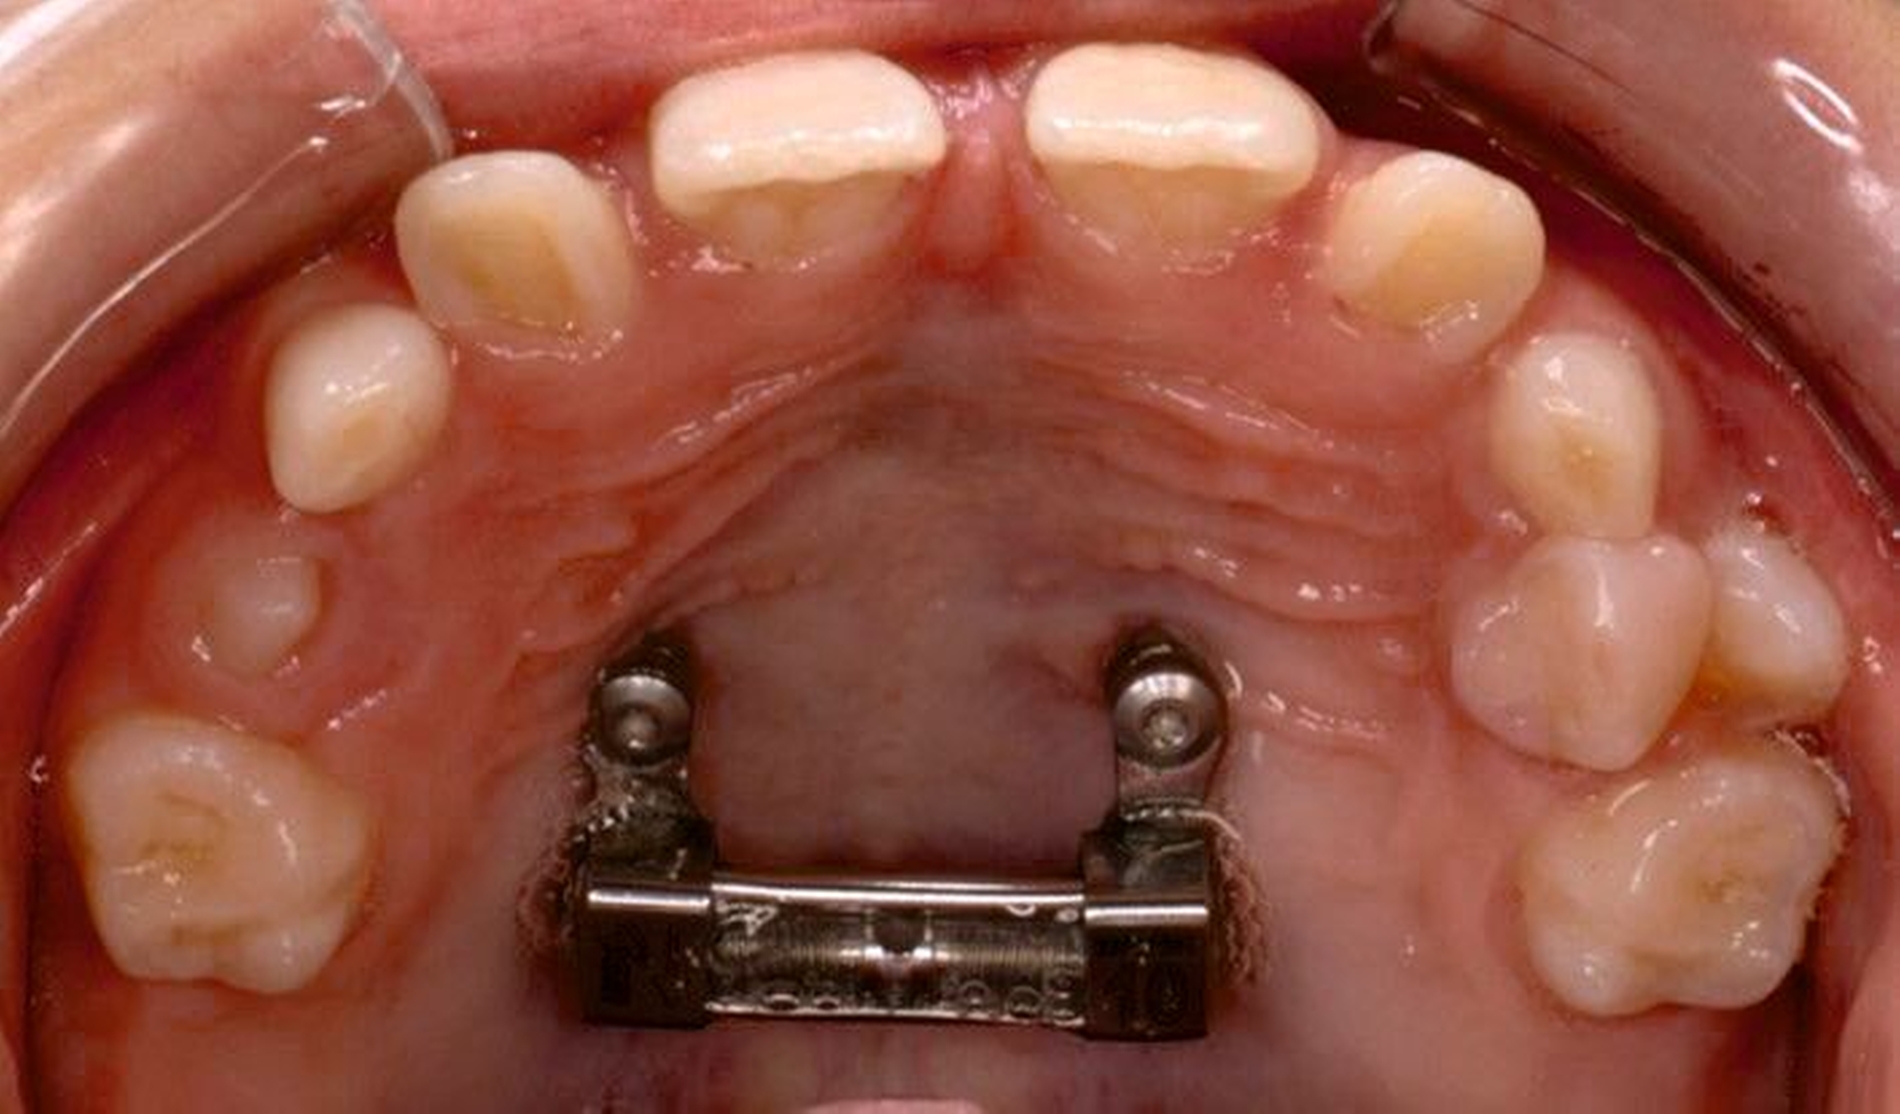

Die Eltern des Patienten wurden angewiesen, die Schraube einmal täglich zu aktivieren. Die gesamte Aktivierungszeit der Hyrax-Schraube betrug circa zehn Wochen. Während dieser Zeit vergrößerte sich die transversale Dimension des Oberkiefers um sieben Millimeter im posterioren Bereich (Milchmolaren) und um fünf Millimeter im anterioren Bereich (Milcheckzähne). Währenddessen trat ein mediales Diastema auf (Abbildungen 4b und 4c), das auf eine skelettale transversale Expansion des Oberkieferknochens hinwies. Nach der aktiven Expansionsphase der Hyrax-Apparatur wurde das Gerät für weitere Behandlungszwecke verwendet: Erstens als Retentionsgerät, um die bereits erzielte transversale Oberkieferbreite zu halten und zweitens als skelettal verankerte Apparatur zum Einstellen der retinierten und verlagerten Zähne mithilfe individuell angefertigter Kragarme. Hierfür wurde die Hyrax-Apparatur im zahntechnischen Labor modifiziert, indem Kreuzröhrchen für eine stationäre Befestigungen für die Drähte des Kragarms angebracht wurden.